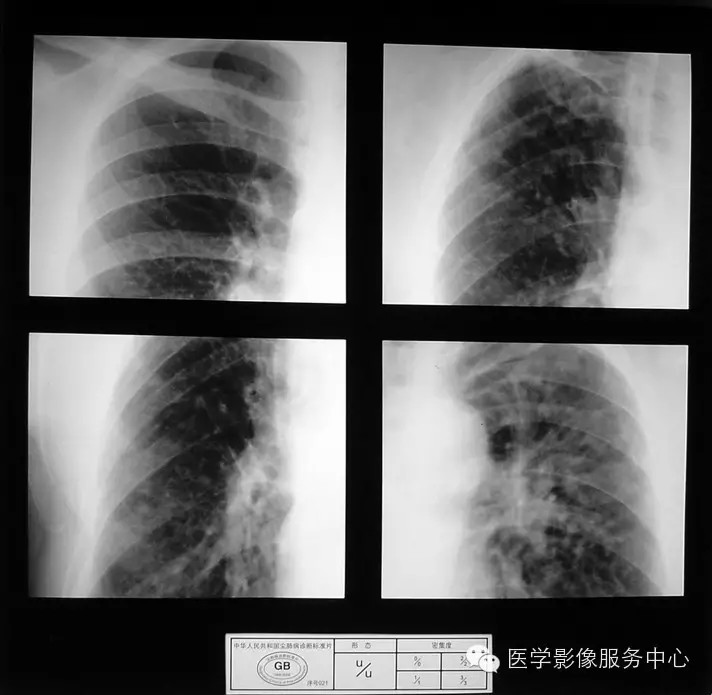

4.3 二期尘肺(Ⅱ)

a)Ⅱ:有总体密集度2级的小阴影,分布范围超过4个肺区;或有总体密集度3级的小阴影,分布范围达到四个肺区。

b)Ⅱ :有总体密集度3级的小阴影,分布范围超过4个肺区;或有小阴影聚集;或有大阴影,但尚不够诊断为Ⅲ者。